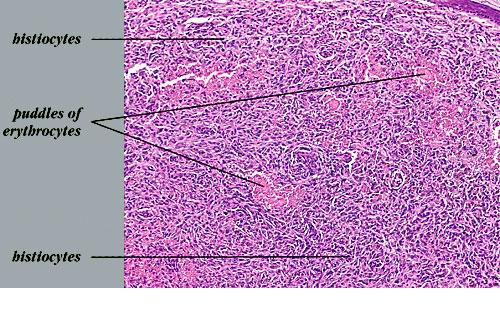

The bulk of the tumor is within the mid dermis where no capsule is present and the periphery of the lesion blends with the surrounding tissue. Whorling fascicles of a spindle cell proliferation with excessive collagen deposition are characteristic. At the periphery, the spindle cells characteristically wrap around normal collagen bundles (see the images below). Occasionally, melanocytes have been reported to be interspersed amongst the spindle cells.24